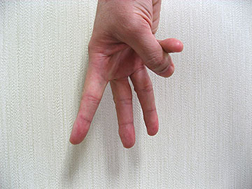

下の写真をご覧下さい。

正面から撮影した手ですが、指が2本見えています。

そして次の写真をご覧下さい。違う方向から撮影したら指は3本うつっています。

さらに一本目と二本目との間隔は開いていますが、二本目と三本目との間隔はほとんどないことがわかります。このようなことが現実に歯科の治療現場で起きているのです。

つまり、先ほども申し上げたように「開いて開けてみないとわからない」「インプラントを埋めてみないとわからない」ということです。手術の翌日、患者さまの元気そうな顔を見て内心ホッとしているのが現状なのです。